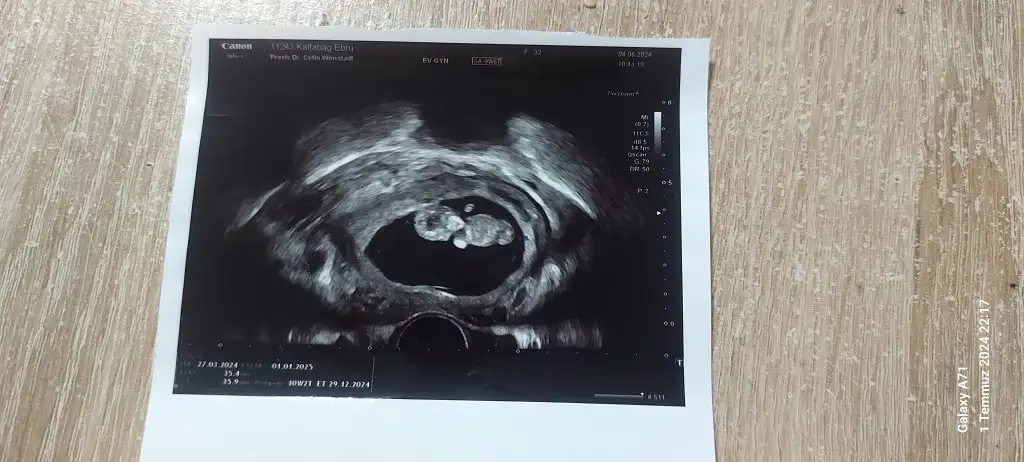

Burada bebeğin konumununa göre yorum yapmışlar ama ramzi teorisi plasentanın konumuna göre bilgi veriyor diye biliyorum ben. Plasentanın da nerede olduğunu göremedim 2 gündür:)Konu biteli yıllar olmuş ama belki yorum gelir 7+4 karındanEki Görüntüle 3454856

Karından hepsiBenimkinede bakar mısın rica edersem